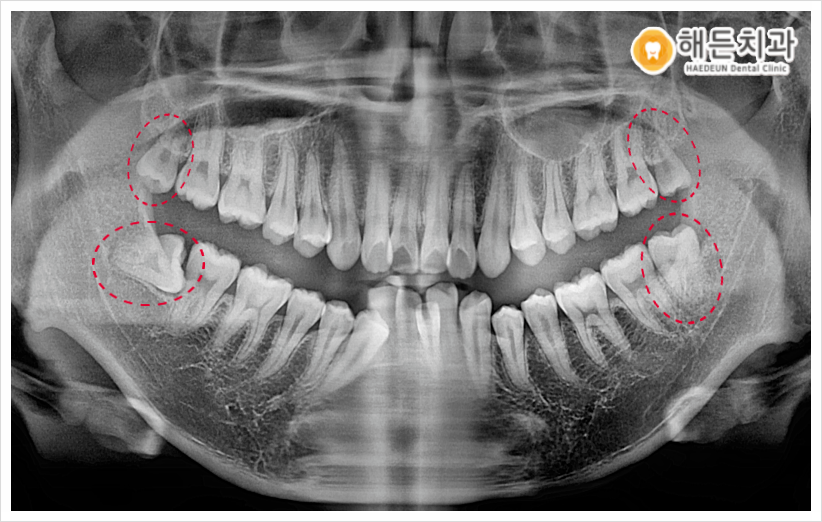

오늘 소개해 드릴 분께서는 오른쪽 아래 사랑니 주변이 불편하다며 본원을 찾아주셨는데요. 평소 음식물도 잘 끼고 잇몸이 부었다 가라앉았다 반복해 왔다고 말씀해 주셨습니다.

파노라마 사진을 촬영하여 확인해 보았더니 사랑니가 위아래 모두 맹출이 되어있었으며, 오른쪽 아래를 제외한 나머지 3개는 비교적 올바른 방향으로 맹출이 되어있었는데요.

하지만 위치적 특성상 맨 안쪽에 위치해 있다 보니, 칫솔질의 접근이 어려워 위생관리가 잘되지 않는 상태였습니다.

이 경우 계속 방치하게 되면 차후 충치가 생기거나 주변 치아에도 영향을 끼칠 수가 있기 때문에, 위생적인 구강 관리를 위해서는 발치하는 것이 좋다고 판단이 되어 환.자분과 꼼꼼한 상.담을 진행한 후에 사랑니 4개를 모두 발치하기로 계획하였습니다.